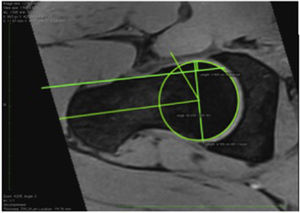

Cam lesions were evaluated by measuring the alpha angle on the axial oblique reconstruction between the axis of the femoral neck and a line connecting the centre of the femoral head to the start point of the sphericity of the head-neck contour. Subjects with an alpha angle >55° were diagnosed with a cam-type impingement.7–20

A diagnosis of pincer-type impingement was principally established by a centre edge angle measurement >39° (FAI), which is an indicator of excess acetabular coverage. The FAI was measured on the coronal plane between a vertical line passing through the centre of the femoral head and another line from the centre of the femoral head to the lateral acetabulum.21–23

With regard to the type of FAI, there was a prevalence of 22.5% (n=18) of cam-type lesions, and of 1.3% of both pincer and mixed lesions (n=1) (Fig. 2). We found 33.8% labral lesions, and 18–8% (n=15) intrasubstance degeneration, 12.5% partial labral tear (n=10), and 2.5% complete labral tear (n=2) (Fig. 3). The prevalence of femoroacetabular cartilage lesions was 13.8% of the hips assessed, and we found acetabular cartilage lesions in 6.3% (n=5), this percentage was in turn distributed into 5% (n=4) with cartilage softening and oedema, and into 1.3% (n=1) with subchondral bone fissures >1.5 in diameter; 75% (n=6) had femoral cartilage lesions. An acetabular cyst was present in 5% (n=4) of the population. Chondrolabral damage was seen in 10% (n=8) and synovitis in 1.3% (n=1). Other findings were femoral head oedema in 5% (n=4), capsular or ligament thickening in 2.5% (n=2), coxa profunda in 17.5% (n=14) and labral or paralabral cyst in 1.3% (n=1). None of the players had cysts in the femoral head-neck union, round ligament impairment, retroversion or Os acetabuli.